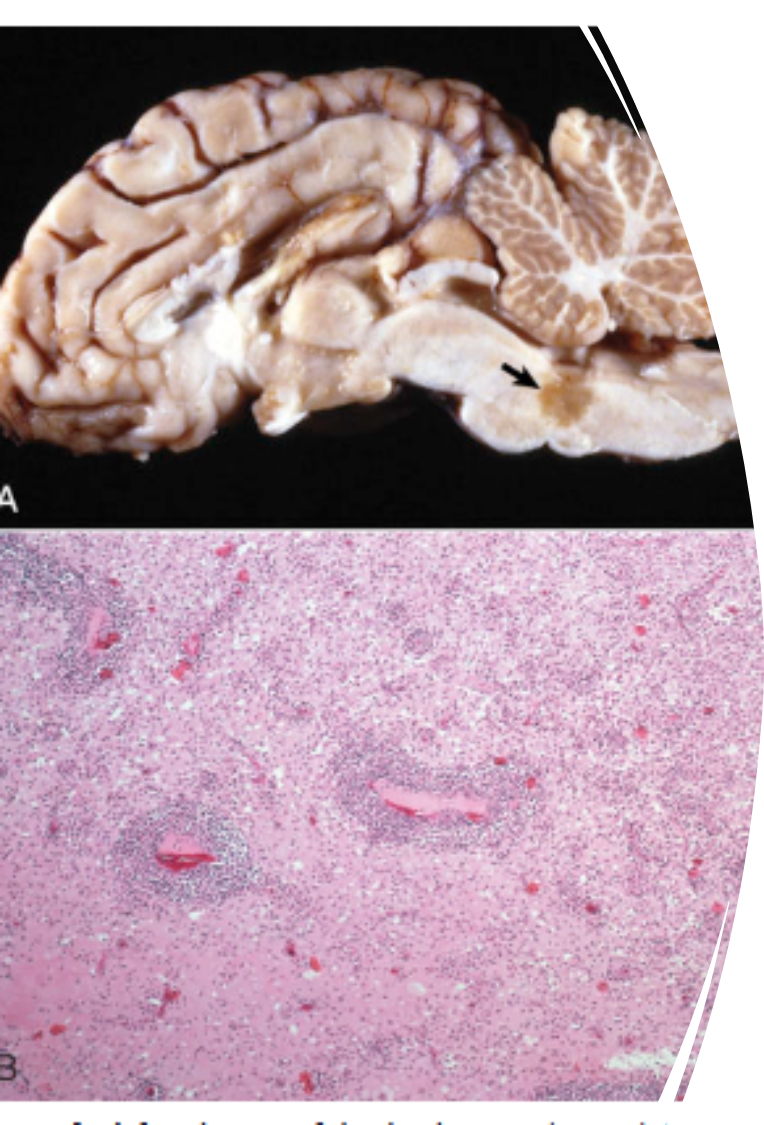

What pathology is shown in this image?

Trigeminal nerve schwannoma

Spinal nerve schwannoma